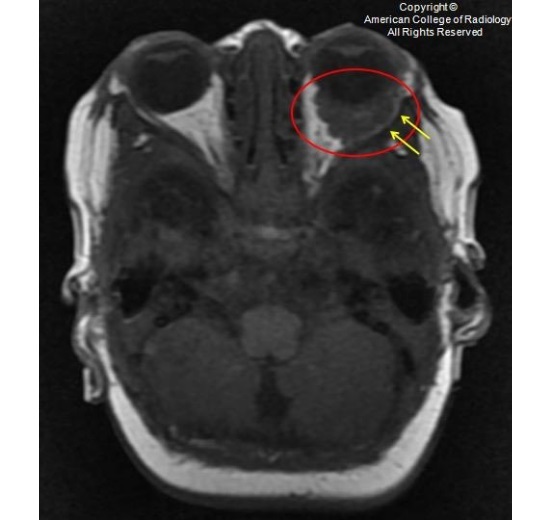

图 2 为 T2,眼眶内可见一均匀长 T2 信号(红圈),未侵及眶内肌肉和神经(白色箭头)。外前方可见一流空信号(黄色箭头)

图 3 为 T2,眼眶内可见一均匀长 T2 信号(红圈),未侵及眶内肌肉和神经(白色箭头)。外前方可见一流空信号(黄色箭头)